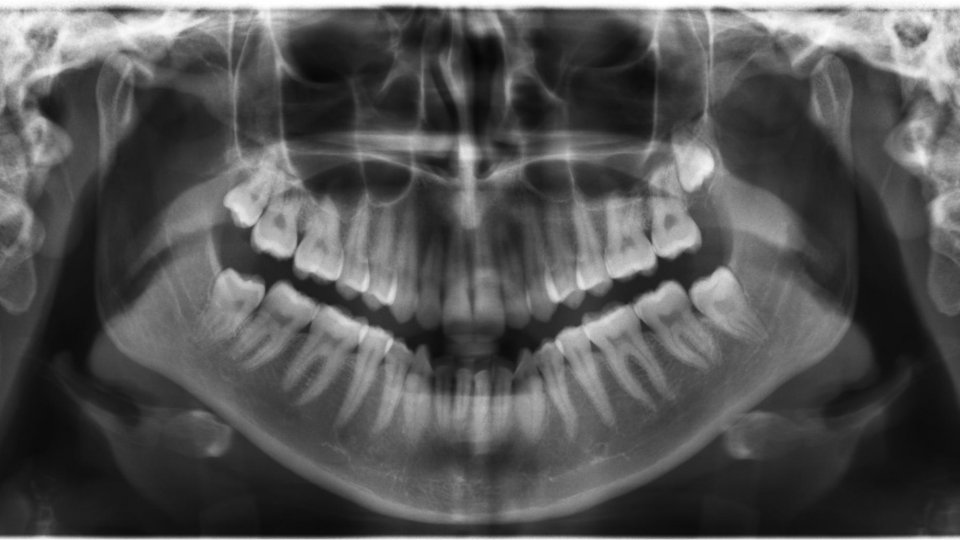

Kezelések előtt, az első találkozáskor egy vizsgálat alkalmával felmérjük fogazatának állapotát, szükség esetén készítünk egy digitális panoráma Rtg. felvételt és ezek alapján megbeszéljük az Ön kezelési tervét és árajánlatát.